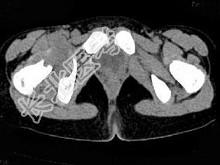

- 单项选择题女,11岁, 肺部有结核病史,二个月前右髋关节有外伤史, 右髋关节部逐渐肿胀疼痛,休息后可减轻, 结合图像,最可能的诊断是 ( )

A、右髋关节结核

B、化脓性关节炎

C、右髋关节退行性变

D、右髋关节类风湿关节炎

E、右髋关节痛风